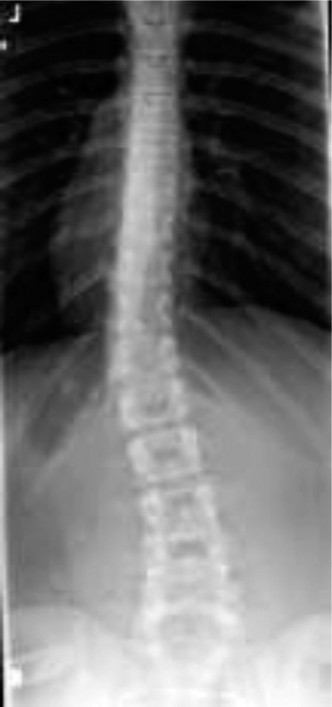

CASE 39 Dr. Coleen S. Sabatini A 12-year-old, premenarchal girl has been referr…